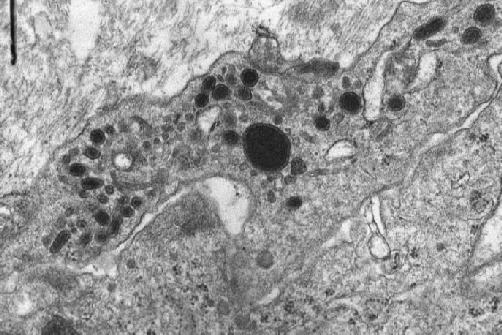

Operation specimen (jpg.20KB) (OMH 98-0339): Primary pulmonary artery sarcoma, open thoracic surgery - intimal sarcoma (HE stain [jpg.44KB]), with involvement of the pulmonary valve. Electron microscopic examination reveals elongated cells (jpg.52KB) and occasionally multipolar giant cells (jpg.75KB) with irregulary indented nuclei, whose cytoplasm contains electron-dense inclusion bodies that measure 500 nm in largest diameter (jpg.46KB), suggesting of lysozomal origin but being somewhat similar to neurosecretory granules. No basal lamina is formed near the tumor cells.